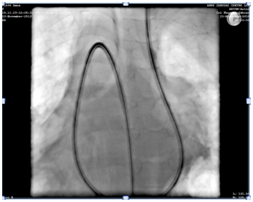

Chest X-ray revealed cardiomegaly with lung plethora. There were additional patchy infiltrates scattered over the lung fields bilaterally (Figure 1). Transthoracic 2D echocardiography confirmed mirror image dextrocardia with a large conical PDA measuring 07 mm at its slenderest point in parasternal short axis and suprasternal views and with volume overloaded left atrium & ventricle apparent on four chamber apical view. A spectral Doppler placed across the ductus in parasternal short axis view, disclosed a continuous flow with peak systolic pressure gradient of 30 mmHg.

Figure 1 Chest X-ray showed cardiomegaly, and bilateral lung plethora. There were additional patchy infiltrates scattered over the lung fields bilaterally.